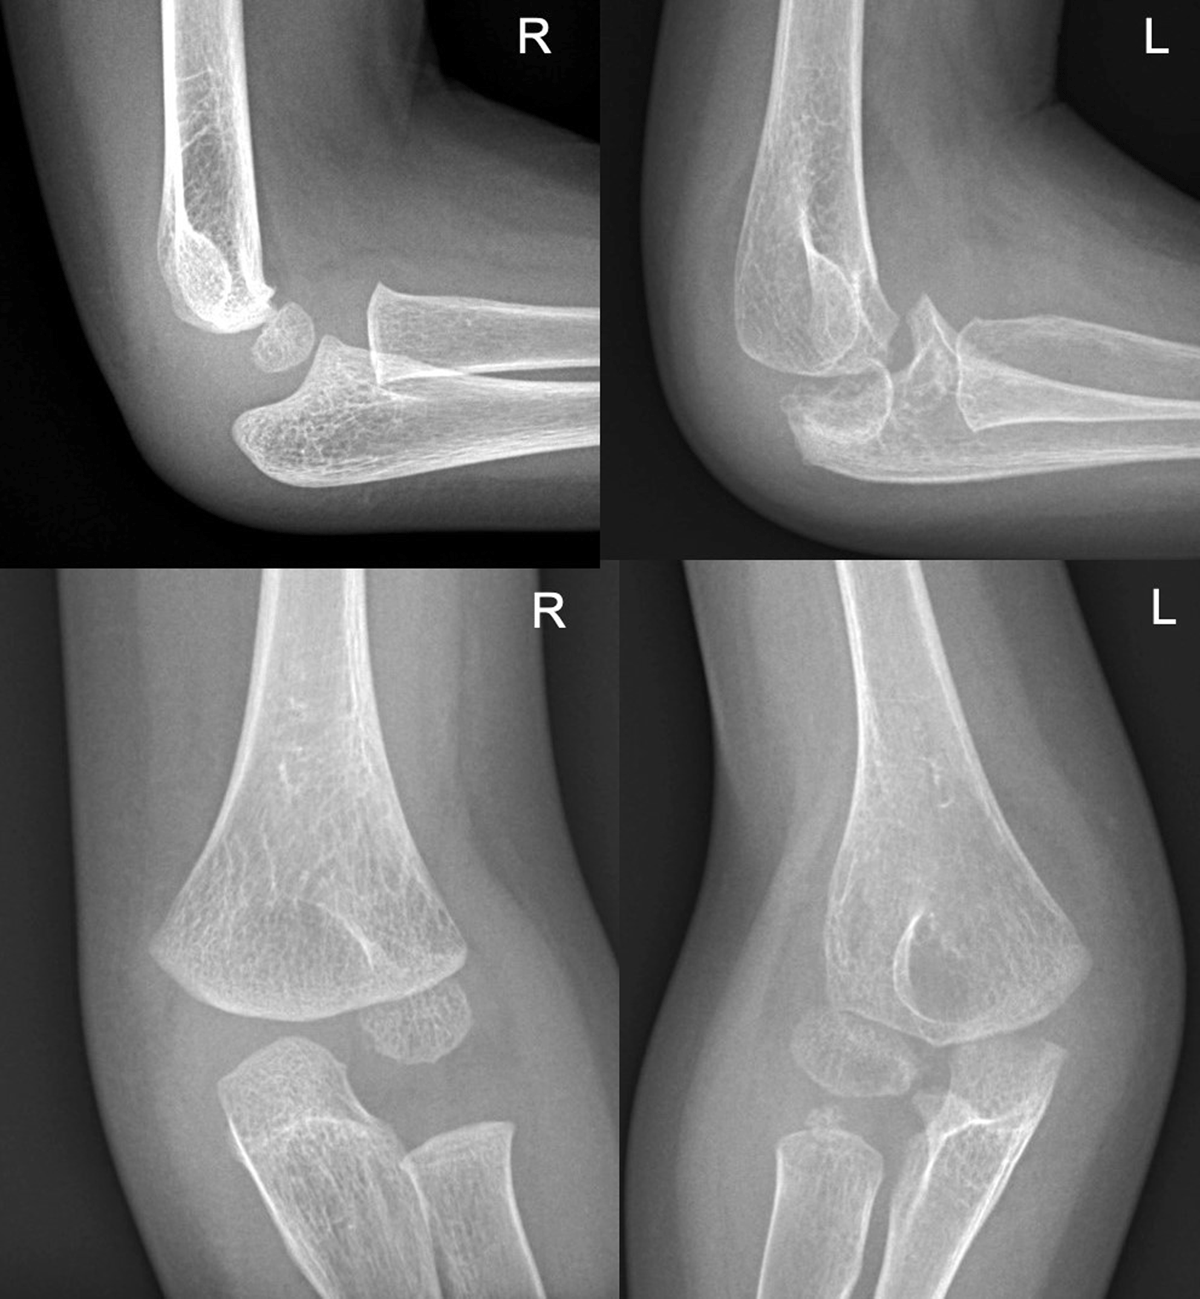

Figure 3

The radiographs of elbows show a significant osteolysis of the left elbow, leading to joint collapse. Soft tissues around the right elbow are swollen. The right elbow appears normal.